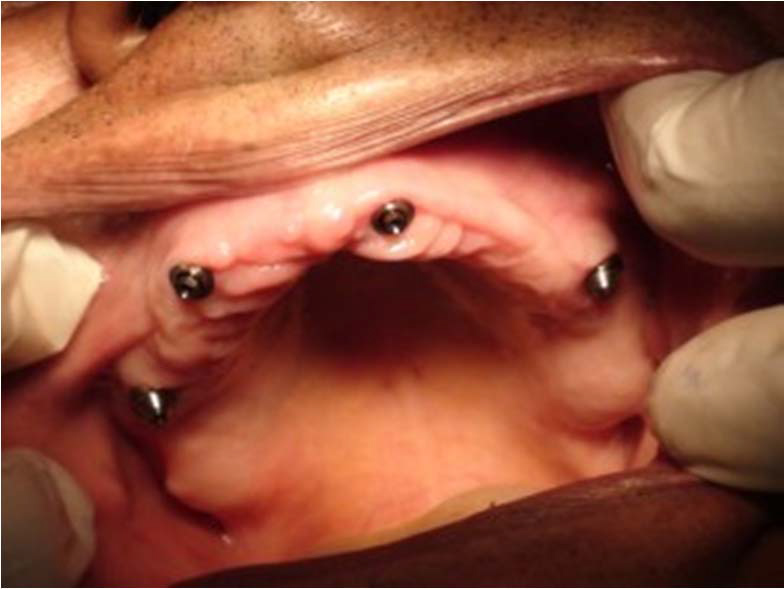

Bezzubá čelist je hlavní indikací pro ošetření pomocí implantátů. Zejména celkové zubní náhrady v dolní čelisti mají velice nízkou stabilitu a držení díky velkému úbytku kosti.

S pomocí zubních implantátů můžeme díky různým kotevním systémům (třmeny, kulové hlavy, Locatory) zajistit stabilitu a držení protézy nebo při použití většího počtu implantátů zhotovit pevné náhrady – můstky nalepené nebo našroubované na pevno na implantáty.

S těmito typy náhrad můžeme dosáhnout perfektní funkci, výbornou estetiku, fonetiku a současně zajistit u pacienta možnost dobré hygienickou péče a čištění, která je pro životnost implantátů velice důležitá.